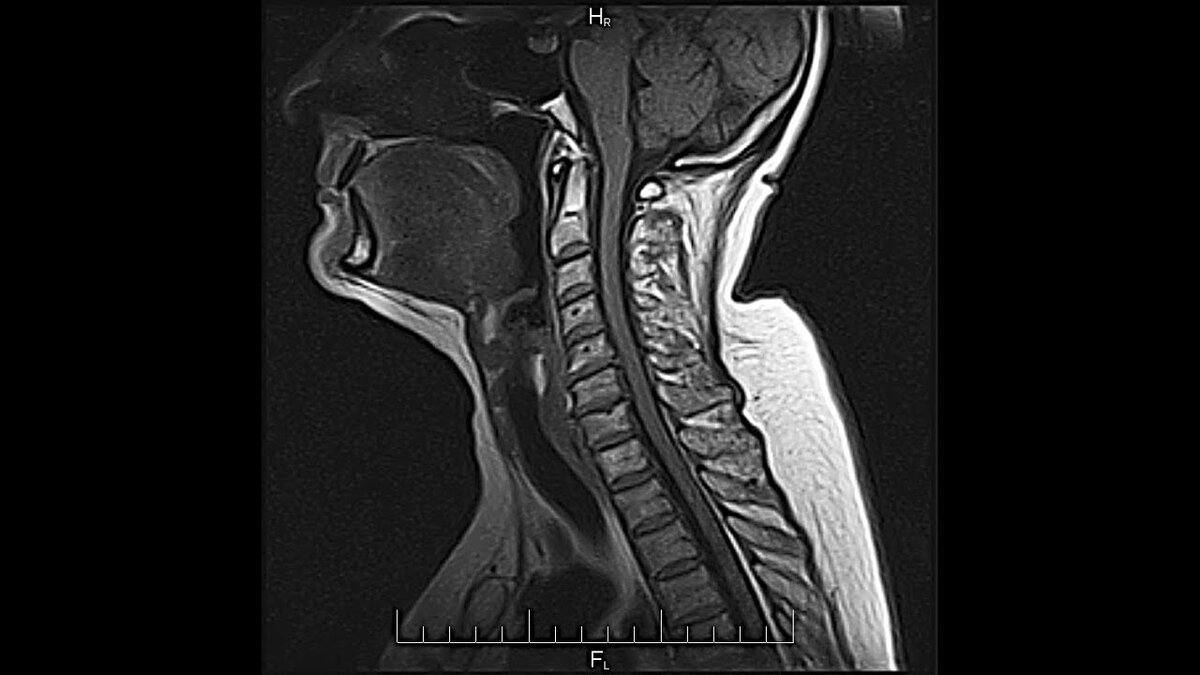

КТ горла и гортани (или мультиспиральная компьютерная томография) - это томографический, то есть послойный, и рентгенологический, то есть с использованием рентген-лучей, метод сканирования. В ходе него высокотехнологичный томограф осуществляет многочисленные снимки горла, глотки, гортани и трахеи под разными углами, а компьютер на основании полученных сканов выстраивает объемные реконструкции данных участков дыхательной системы. Результатом сканирования являются томограммы, на которых врач может увидеть патологические изменения размером до 1 мм. Качество и цена КТ гортани и горла во многом зависят от срезовой мощности томографа и применения контрастного усиления. В медицинских клиниках СПб установлены томографы мощностью от 4 до 128 срезов за один оборот рентгенологической трубки. Чем больше оборотов может делать КТ аппарат, тем детальнее и информативнее будут снимки.

Для качественной компьютерной томографии органов шеи оптимальным считается применение спирального компьютерного томографа со срезовой мощностью 32 среза и выше. Точность диагностики на таких аппаратах очень высока, и врач получает возможность разглядеть образования размером до 2 мм.